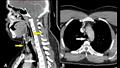

وكشفت الأشعة السينية أنه يعاني من انتفاخ الرئة الجراحي، عندما ينحصر الهواء في أعمق الأنسجة تحت الجلد.

وأظهرت الأشعة المقطعية أن التمزق كان بين العظمتين الثالثة والرابعة من رقبته وأن الهواء يتراكم في الفراغ بين الرئتين في صدره.